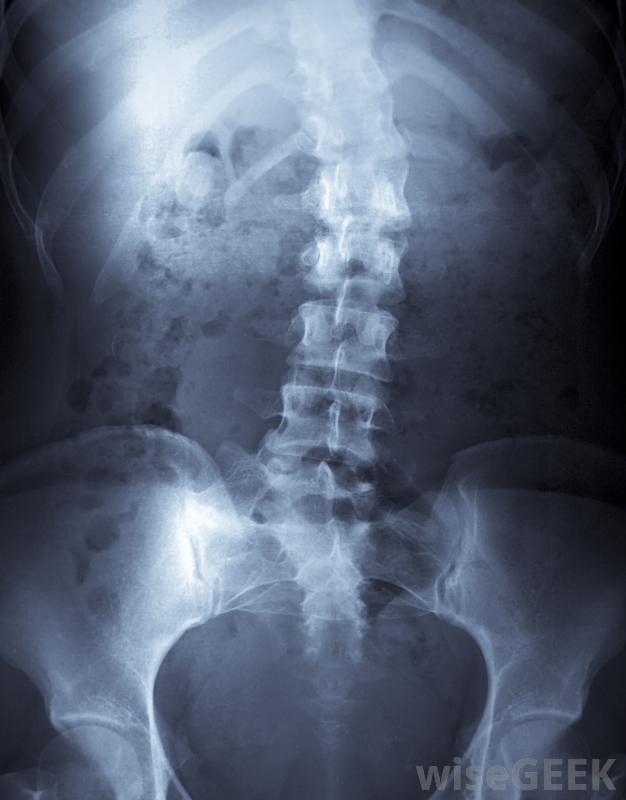

TLSO支架是一种主要用于脊柱侧凸儿童的脊柱支架。该支架安装在躯干上方并支撑背部。除了在脊柱侧凸治疗中的作用外,TLSO支架也可用于背部受伤或背部手术后恢复的成人和儿童。 一些儿童可能需要佩戴支架以防止脊柱侧凸...

TLSO支架是一种主要用于脊柱侧凸儿童的脊柱支架。该支架安装在躯干上方并支撑背部。除了在脊柱侧凸治疗中的作用外,TLSO支架也可用于背部受伤或背部手术后恢复的成人和儿童。

胸腰椎骶骨矫形器支架通过对脊柱各点施加压力来对抗脊柱侧凸。随着时间的推移脊柱让位给背带的压力,背部的弯曲慢慢变直。这种类型的脊柱侧凸矫正器戴在衣服下面,旁观者几乎看不见。戴TLSO支架的儿童通常一天能保持23小时,尽管它通常在剧烈的体力活动中被移除。